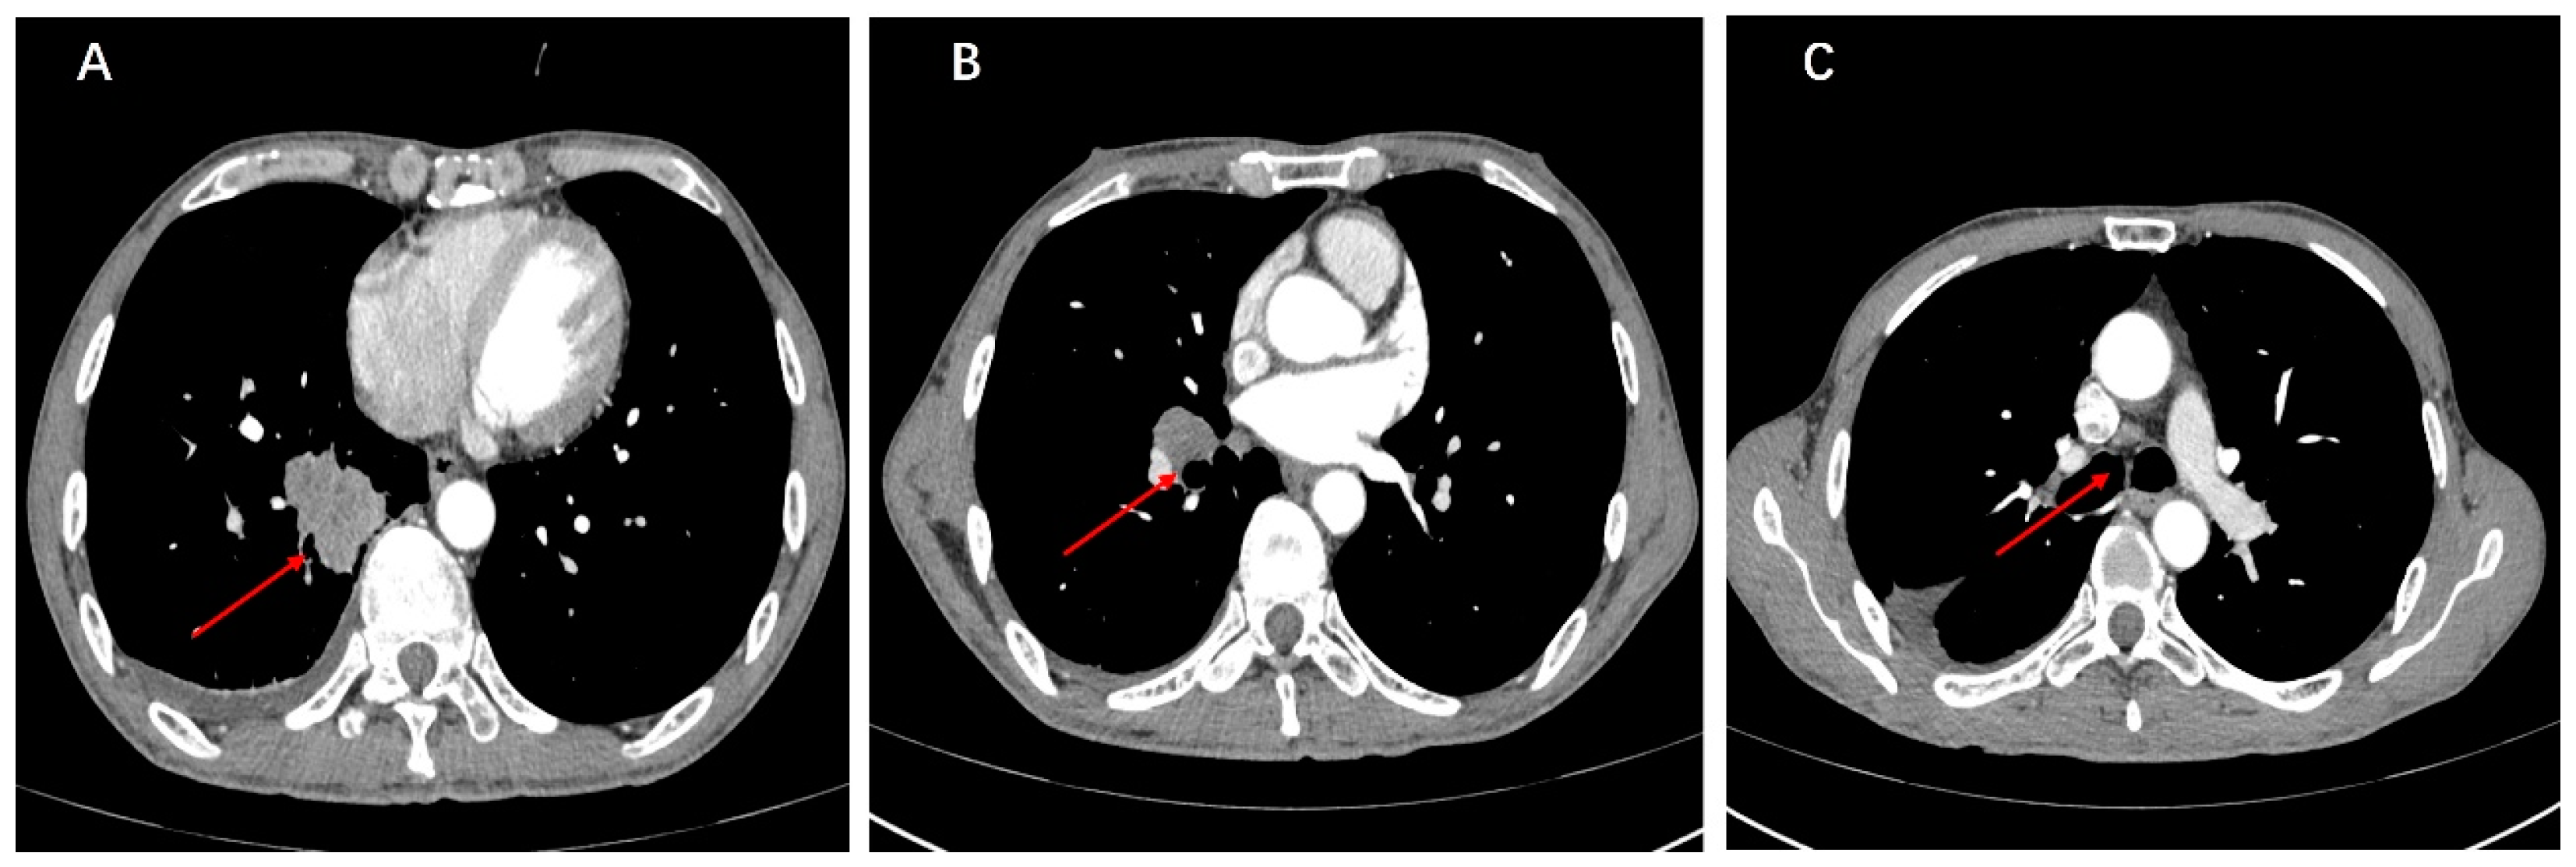

2. Case Presentation